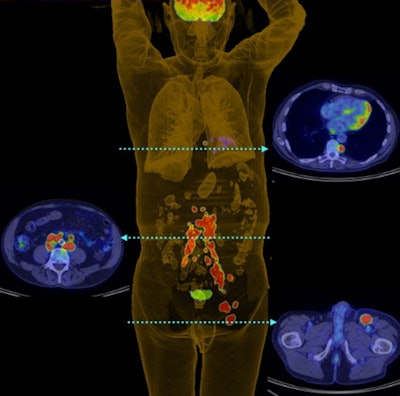

Australian researchers found that FDG-PET scans changed the management plan for more than one-third of patients with Merkel cell carcinoma and altered the disease stage in approximately one in five cases, according to a study in the August issue of the Journal of Nuclear Medicine.

With the information provided by FDG-PET and subsequent changes in treatment plans, overall survival for Merkel cell carcinoma patients was 60% after three years and 51% after five years, according to a team led by Dr. Shankar Siva of the University of Melbourne's department of oncology (JNM, August 2013, Vol. 54:8, pp. 1223-1229).

FDG-PET scans for tumor staging resulted in a change in treatment for 38 patients (37%), the researchers found. Of the 23 scans that were deemed to have a high impact, 14 (62%) resulted in a change in treatment modality, five (21%) changed treatment intent, and four (17%) changed both treatment modality and radiation therapy technique.

Of the five patients for whom the treatment intent changed, four had their cancer upstaged due to distant metastases and were treated with palliative care. The remaining person was downstaged from suspected but unproven distant metastatic disease and received curative care.

Comparing conventional and PET results showed discrepancies in staging for 22 patients, with PET upstaging 17 patients and downstaging five.

Overall survival for the Merkel cell carcinoma patients was 60% at the three-year mark and 51% at five years, according to Siva and colleagues. In addition, overall survival at three years was 78% for patients with PET-staged I/II disease and 37% for stage III cancer. Overall survival at five years was 67% for stage I/II and 31% for stage III.

Five-year overall survival was 39% for those who received surgery only and 42% for those given radiation therapy or chemoradiotherapy only, they added. The rate was 64% for the combination of surgery and adjuvant radiation therapy or chemoradiotherapy.

The results demonstrate FDG-PET's ability to "stratify prognosis with stage, as FDG-PET was the strongest prognostic factor for survival," the authors concluded. "If these results can be validated by similarly large series from other institutions, staging FDG-PET should become part of the standard management of Merkel cell carcinoma."